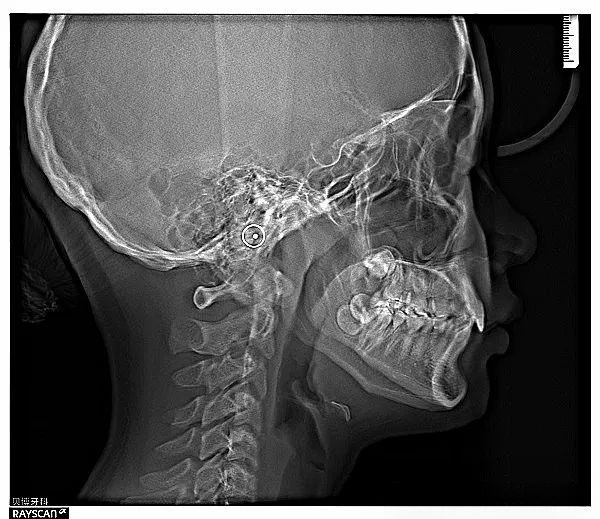

Otsu's 方法因其高效性和易于实现的特点,在多个领域得到了广泛应用,尤其是在医学成像、卫星遥感、文档分析等领域表现突出。特别是在医学成像中,如X射线、CT扫描等图像处理,Otsu's 方法能够有效地帮助医生识别病变区域。在卫星遥感方面,它可用于地物分类、变化检测等任务。此外,对于文档分析,比如文字与背景的分离,Otsu's 方法同样能提供良好的解决方案。这种方法尤其适用于图像直方图呈现明显双峰特征的情形。

Sobel 算子在多种图像处理和计算机视觉任务中都有广泛的应用,包括但不限于边缘检测、图像增强、运动检测和医学成像。在边缘检测中,Sobel 算子是最经典的边缘检测方法之一,能够有效地检测图像中的边缘,广泛应用于图像分割、特征提取等任务。在图像增强中,通过增强图像的边缘信息,Sobel 算子可以改善图像的视觉效果,使其更加清晰。在视频监控和运动检测中,Sobel 算子可以用来检测帧间的边缘变化,从而识别运动物体。在医学图像处理中,Sobel 算子可以用于检测组织结构的边界,辅助医生进行诊断。

Canny 边缘检测器在多种图像处理和计算机视觉任务中都有广泛的应用,包括图像分割、特征提取、物体识别、医学成像和自动驾驶等。在图像分割中,Canny 边缘检测器可以用于检测图像中的物体边界,从而帮助进行图像分割。在特征提取任务中,Canny 边缘检测器可以用于提取图像中的关键边缘特征,为后续的识别和分类任务提供支持。在物体识别中,Canny 边缘检测器可以用于提取物体的轮廓,辅助识别算法进行物体定位和分类。在医学图像处理中,Canny 边缘检测器可以用于检测组织结构的边界,帮助医生进行诊断。在自动驾驶系统中,Canny 边缘检测器可以用于检测道路标志和车道线,辅助车辆导航和避障。